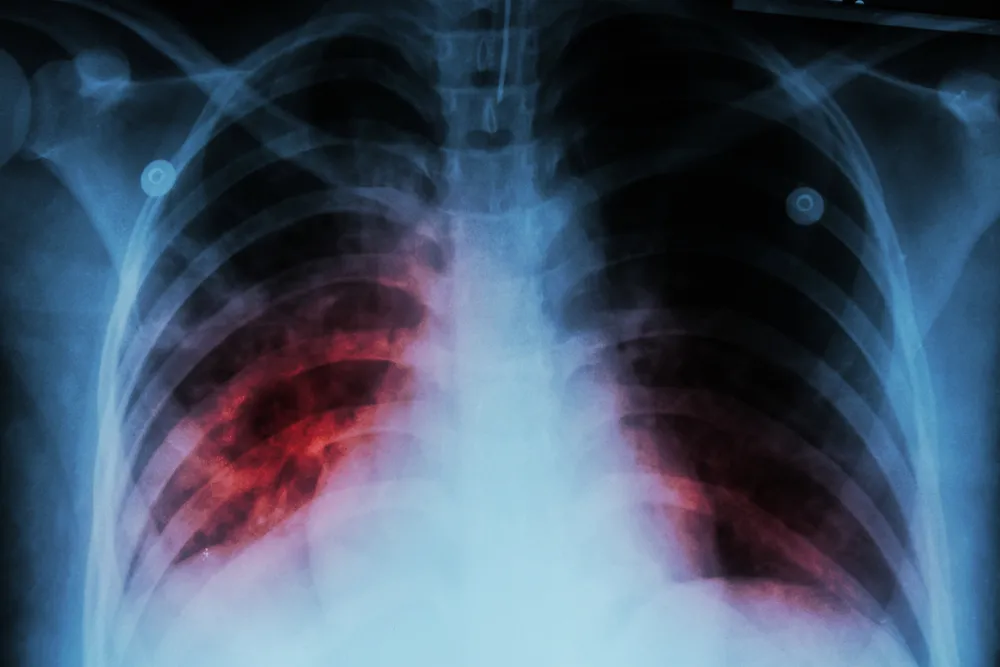

Ever wondered where we got the stethoscope? How about the X-ray? Funny enough, both came from doctors treating tuberculosis. The stethoscope was invented in 1816 by French doctor Rene Laennec, who sought a way to hear the functioning of the lungs and heart.

Sadly, TB took Laennec’s life when he was just 45 years old. About 80 years later, Wilhelm Rontgen used the X-ray to diagnose and follow the development of TV. A few years later he won the Nobel Peace Prize for his discovery.